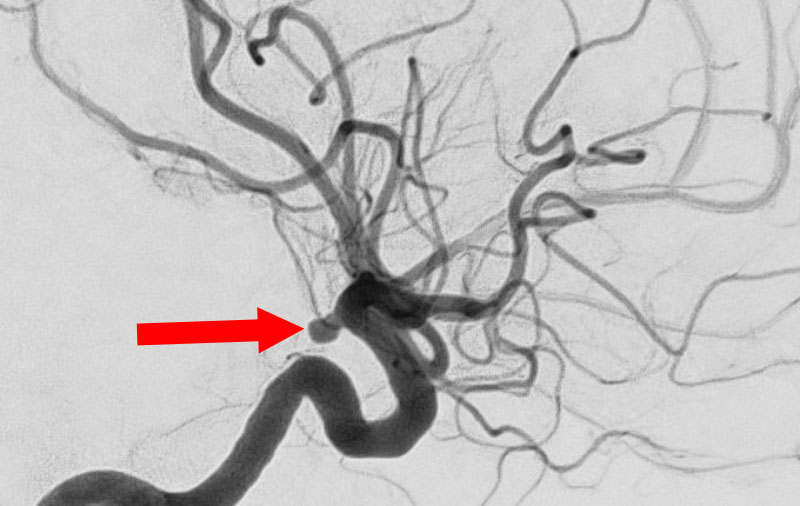

No.1627 手術前